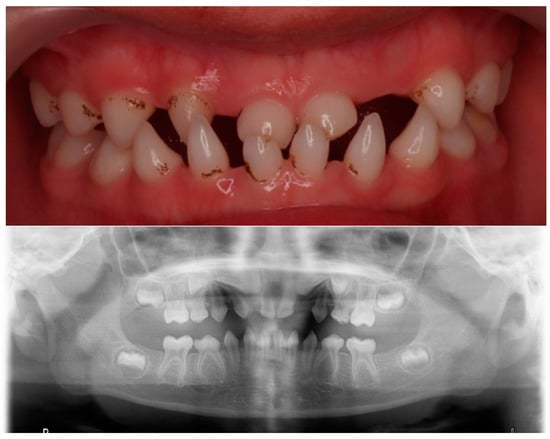

Figure 3.

Clinical and radiographical findings at 11 years old.

The child was followed up by the dentist. At present, the patient is 11 years old with normal psychomotor development, and his dental phenotype showed two conical maxillary central incisors and the first permanent molars. There were still conical-shaped anterior primary teeth and first primary molars. The germs of the second permanent molars were visible (Figure 3). The patient was then monitored by the dentist for treatment planning to address the growth and development of the jaws and subsequent rehabilitative treatment.